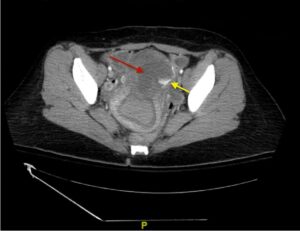

Iatrogenic Uterine Perforation. CT Annotated. JETem 2024